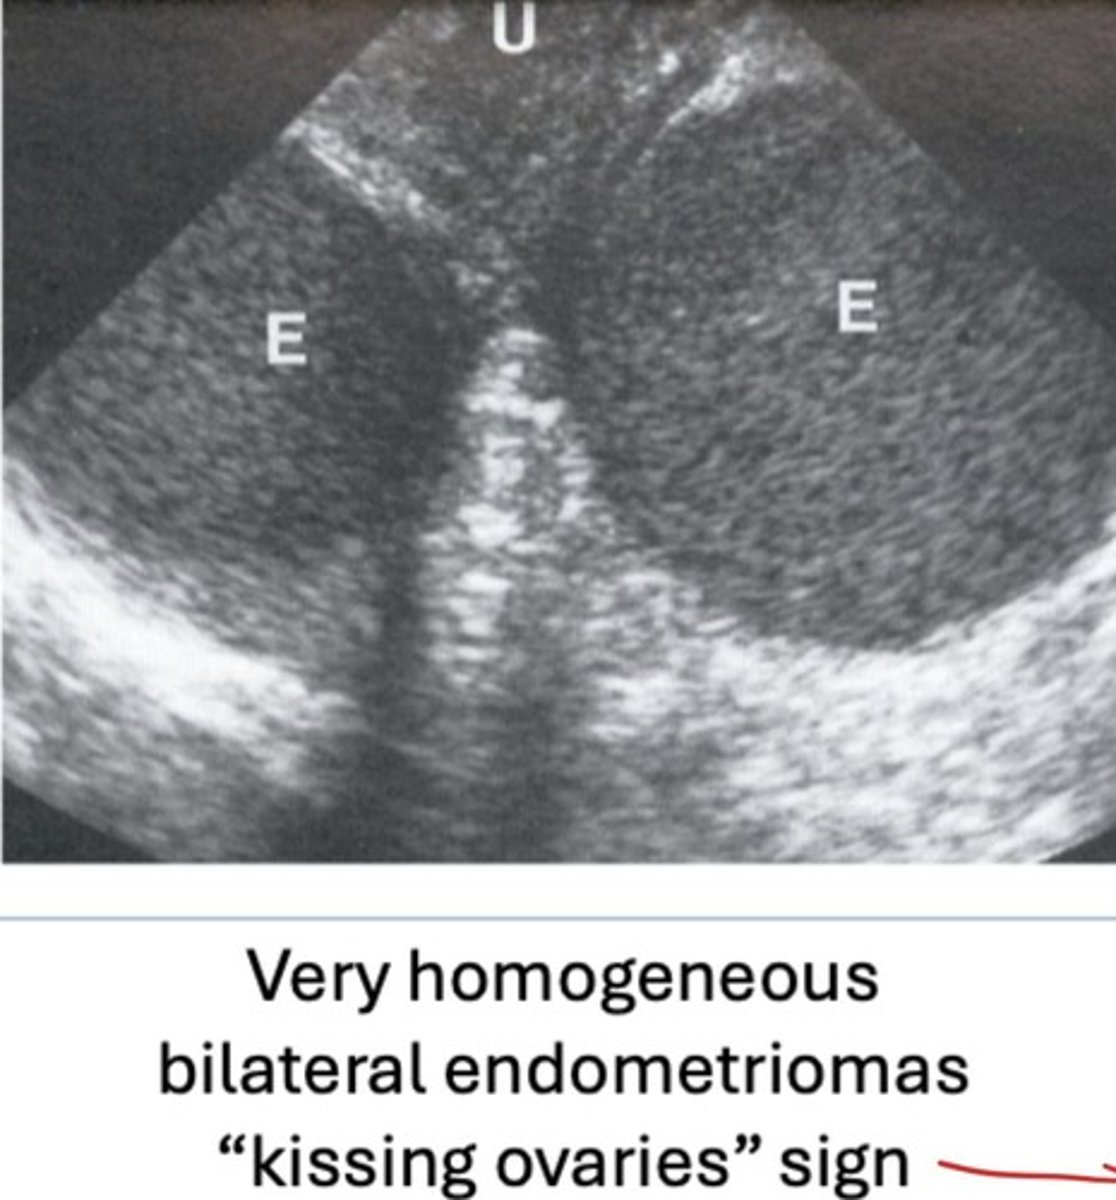

What is the kissing ovaries sign? What condition is this associated with?

- Both ovaries adjacent due to adhesions in pelvis

- Associated with endometriosis/endometriomas

What are the sonofeatures of endometriomas? (HINT: 4)

- Diffuse, homogenous, low level echoes

- Posterior enhancement

- No flow within

- Kissing ovaries sign